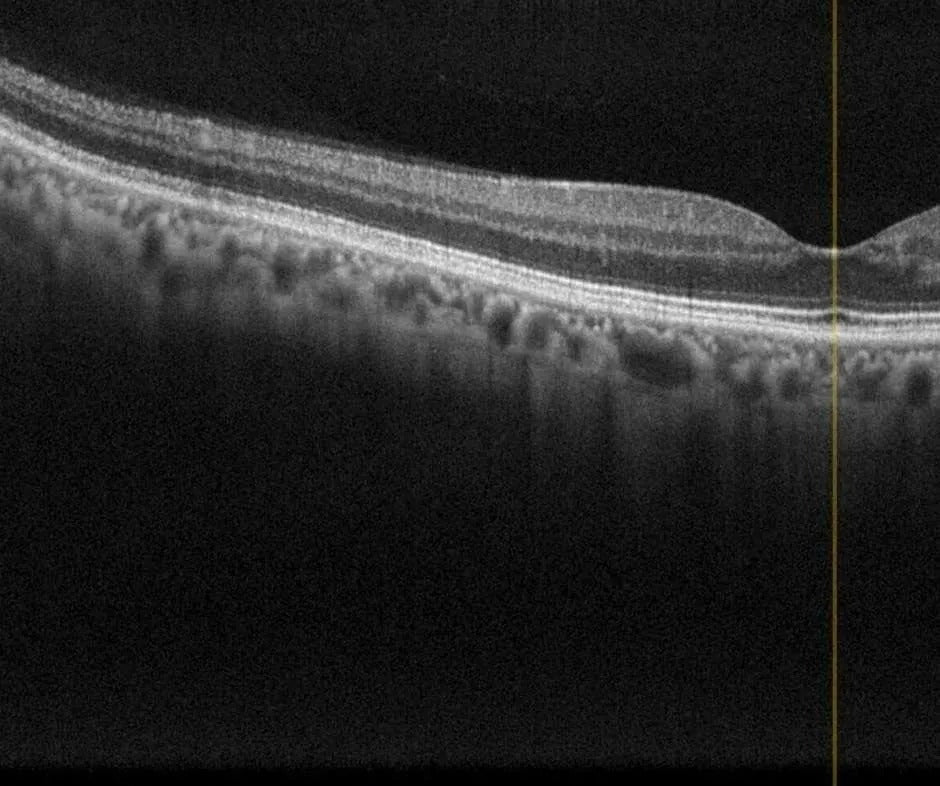

Ocular Coherence Tomography (OCT)

OCT scans are available in our Surrey office and allow for high definition scanning laser images of the retinal layers and optic nerve. This is key in diagnosis and management of glaucoma, macular edema due to diabetic retinopathy, macular degeneration, and many other sight threatening conditions.